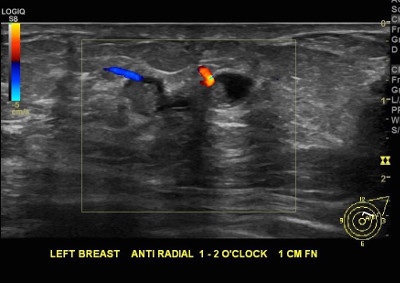

👉In benign papillary lesions, a vascular stalk may be demonstrated on color Doppler scanning while multiple feeding vessels may be seen when imaging malignant papillary lesions.

👉When papillary lesions infarct, the vascular stalk will not be demonstrated.

👉The mural nodule caused by papillary apocrine metaplasia also would not extend into the duct as the papillary lesion shown in the image does.